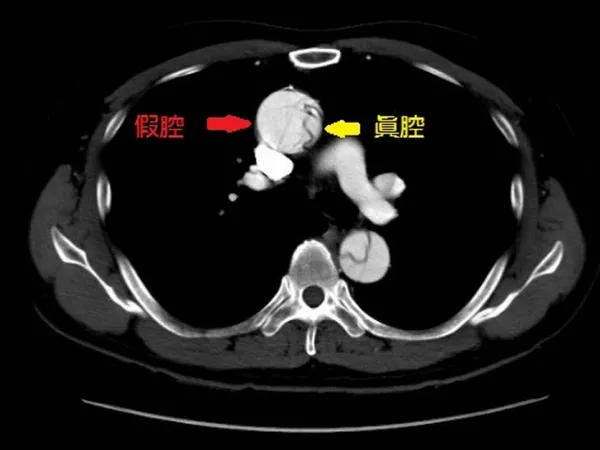

上腹痛竟是「胰臟假性囊腫」 內視鏡導引經胃引流除病灶

55歲的劉先生,因長期喝酒導致糖尿病、慢性胰臟炎,五年前因上腹痛至某醫學中心就醫,診斷為遠端胰管狹窄遂置放胰管支架,疼痛雖有改善,但為避免胰管堵塞,每三個月都要再進行內視鏡手術更換支架且近年來每次更...